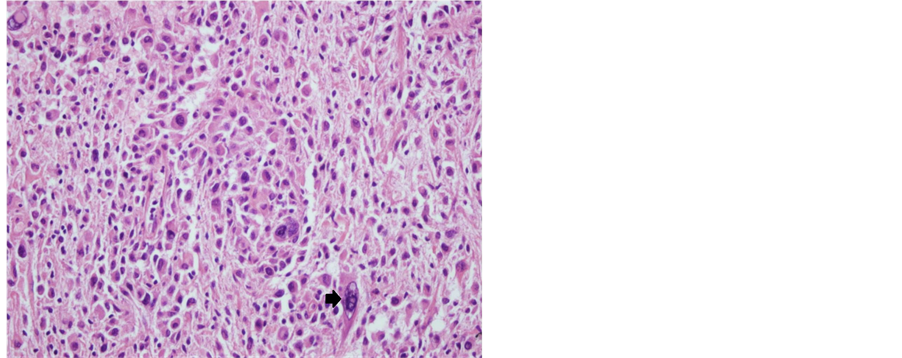

A 32-year-old male patient presented with a generalized epileptic seizure. Neurological examination was normal. Cerebral computerized tomography (CT) and magnetic resonance imaging (MRI) revealed a small solid lesion localized at the frontal lobe, without clear dural attachment, inhomogeneously hyperdense/hyperintense, with irregular enhancement after contrast injection (Figure 1). The patient underwent operation with a preoperative diagnosis of high grade glioma. Histopathologically a dense hypercellular glial tumor was observed. Histopathological and immunohistochemical features (Figure 2 and Figure 3) are summarized in Table 1. A diagnosis of APXA was given. Six months later control MRI revealed a recurrent mass lesion. The morphologic features of the recurrent tumor were similar with that of the primary tumor except for that necrosis was present in the recurrent tumor. Histopathological and immunohistochemical features (Figure 4) are summarized in Table 2. Recurrent tumor was also diagnosed as APXA. In both tumors BRAF V600E mutation was detected by FISH method. p16 mutation was not observed.

Figure 2. Tumoral cells were prominently pleomorphic cells with foamy, xanthomatous cytoplasm, nuclear inclusions and multinuclear giant cells (arrow) (Case 1―primary tumor; H&E, 200×).